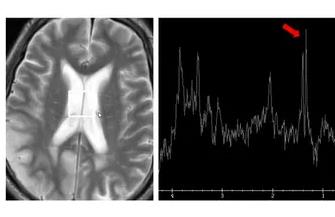

- 【高清01】磁共振病例分析-MELAS

【高清01】磁共振病例分析-MELAS

【高清01】磁共振病例分析-MELAS